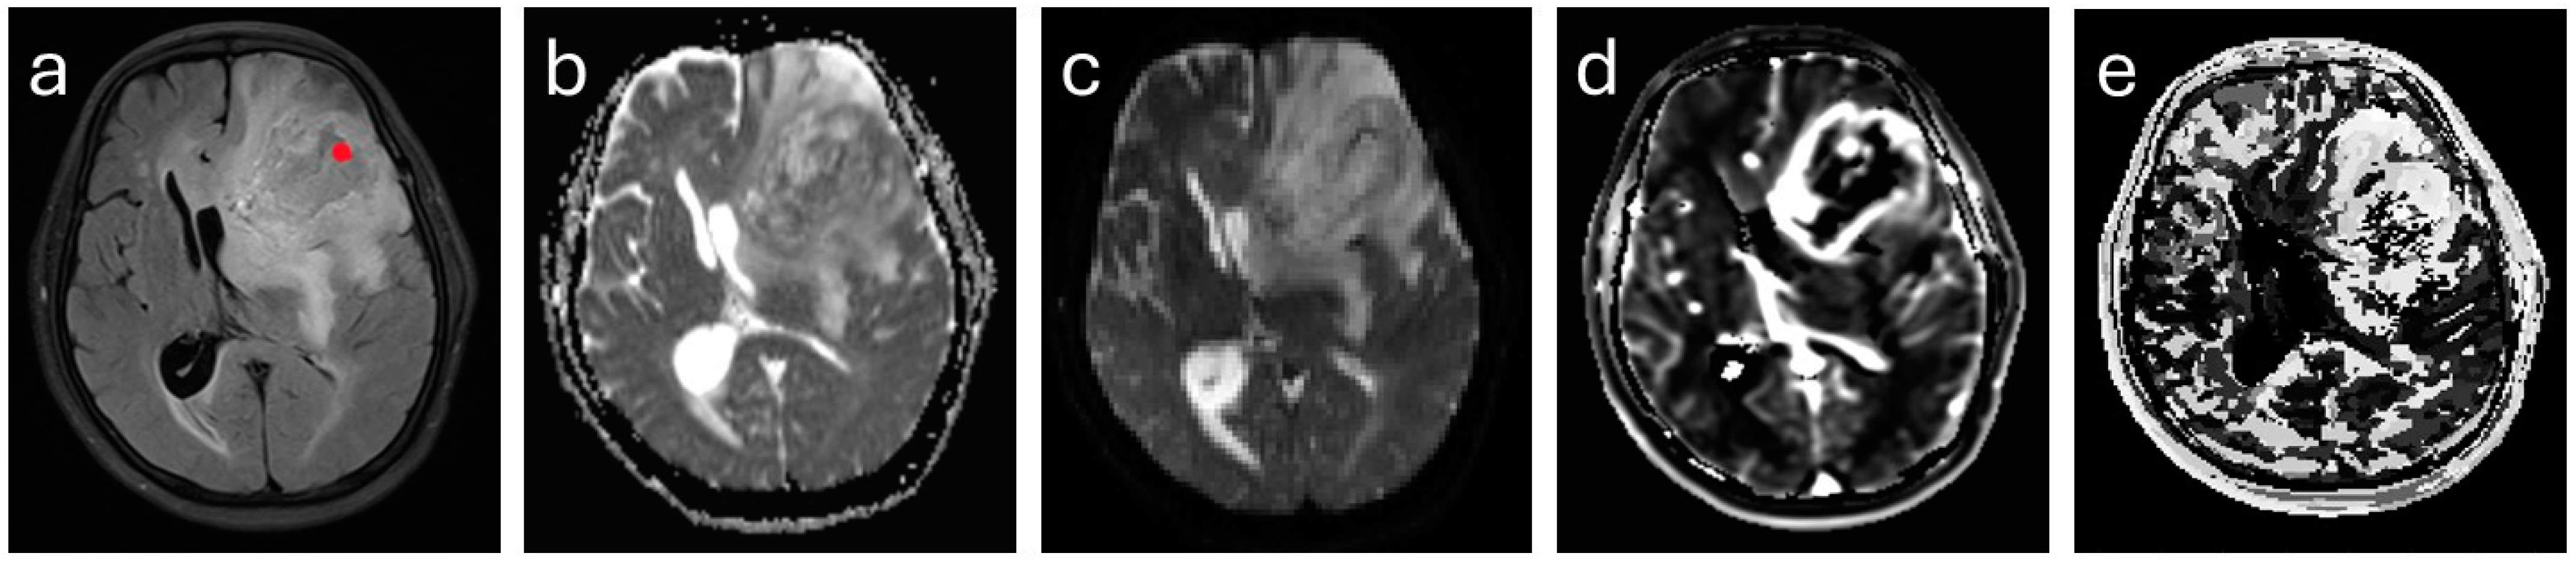

2.3. MR Imaging

2.4. Image Analysis